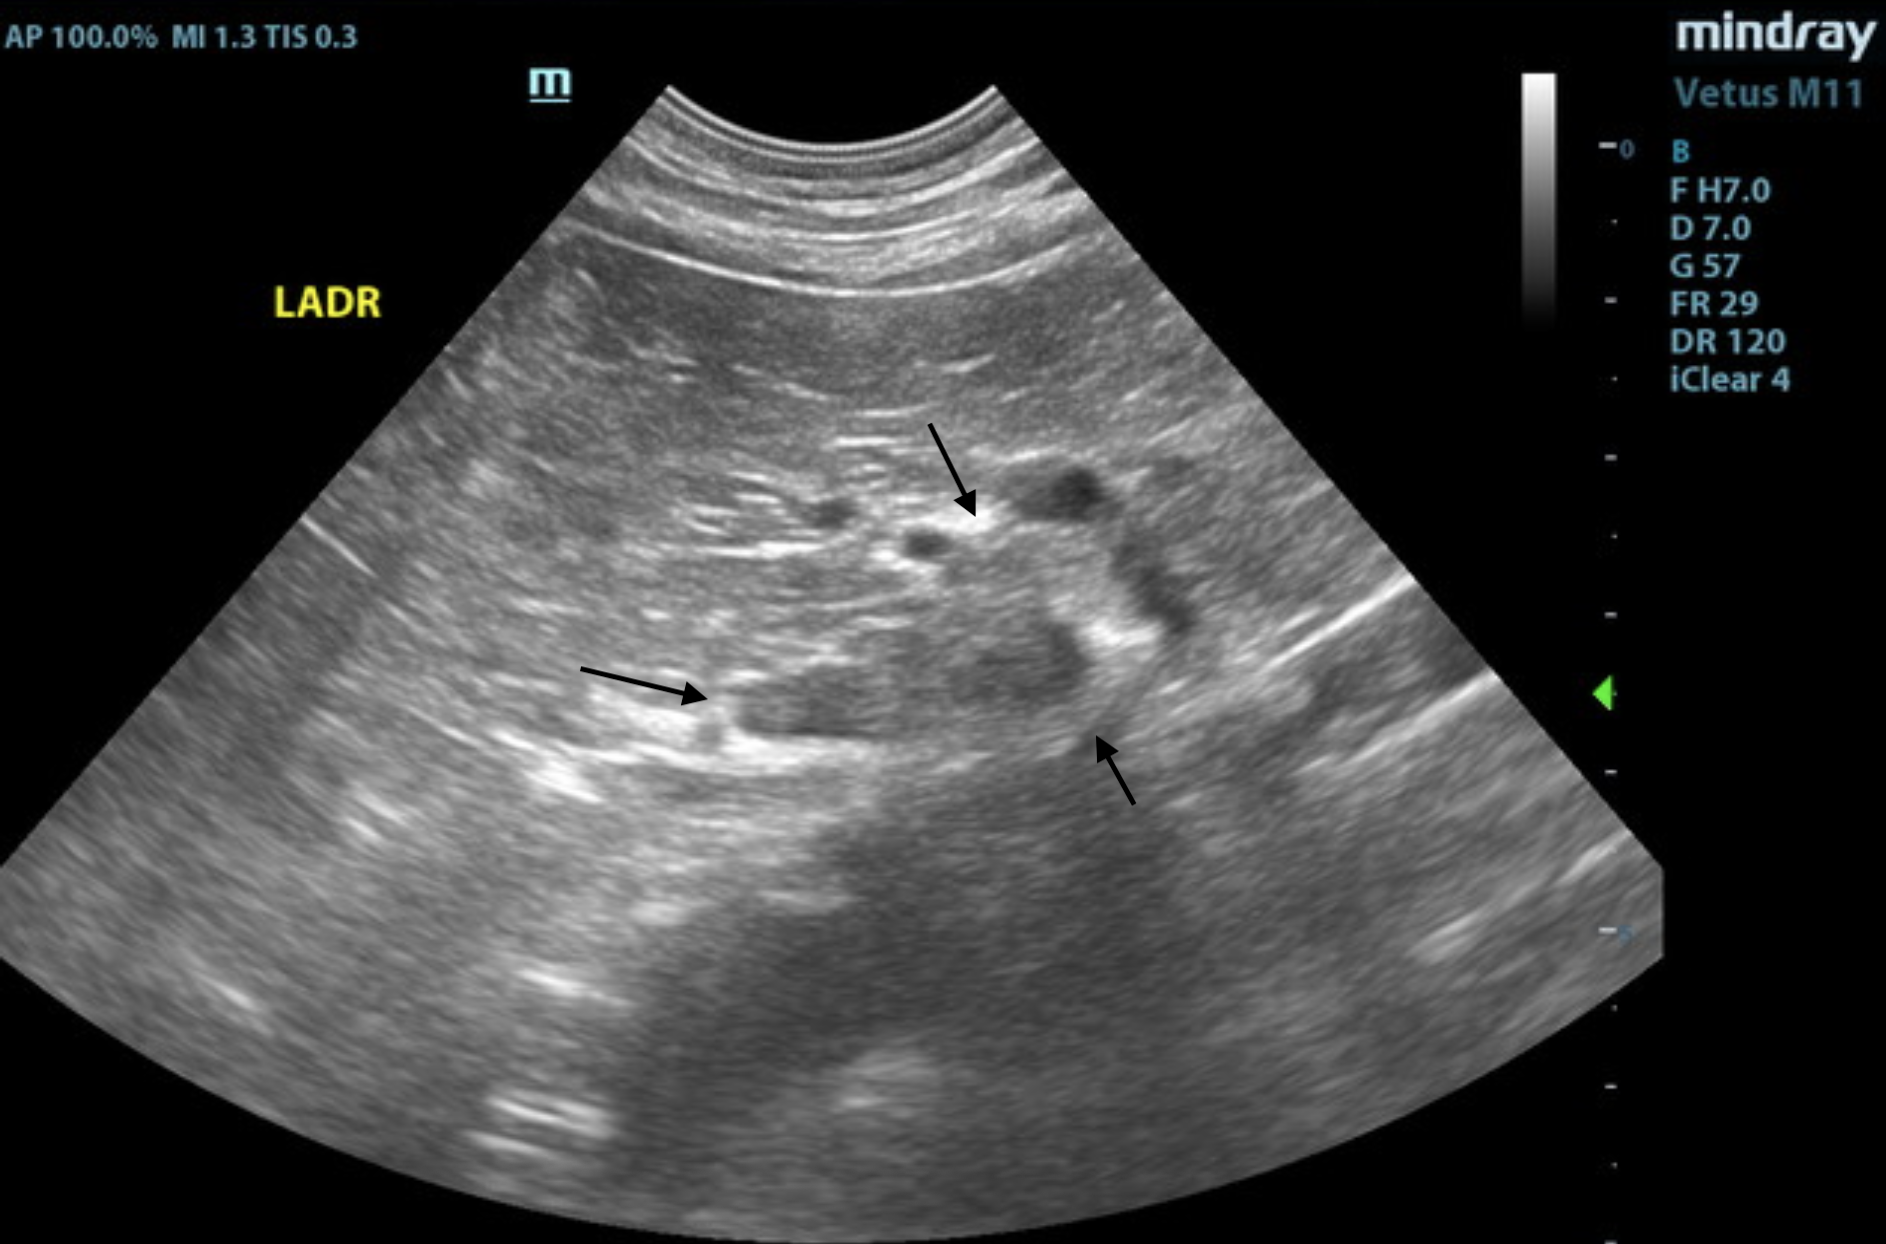

Video 1. Video of the left adrenal gland showing the enlarged, irregular caudal pole.

The left adrenal gland was enlarged at the caudal pole, measuring 0.93 cm at the caudal pole and 0.46 cm at the cranial pole and 2.25 cm in length. It was irregular in contour with capsular expansion. Minor heterogeneity noted at the phrenic vein, consistent with phrenic occupation. Mineralization was also noted.